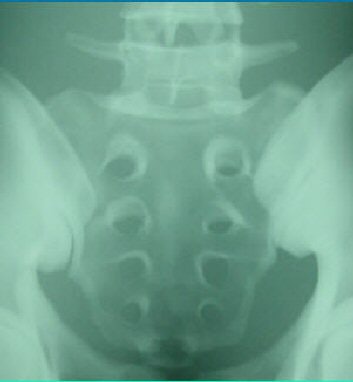

| The image above is from a CR system; the image below is from a DR system before standardizing the images. The pelvis phantom was imaged at a surface-to-image distance (SID) of 40 inches (100 cm), 80 kVp, and 50 mAs. Image courtesy of Larry Frederick and David Piazzo. |